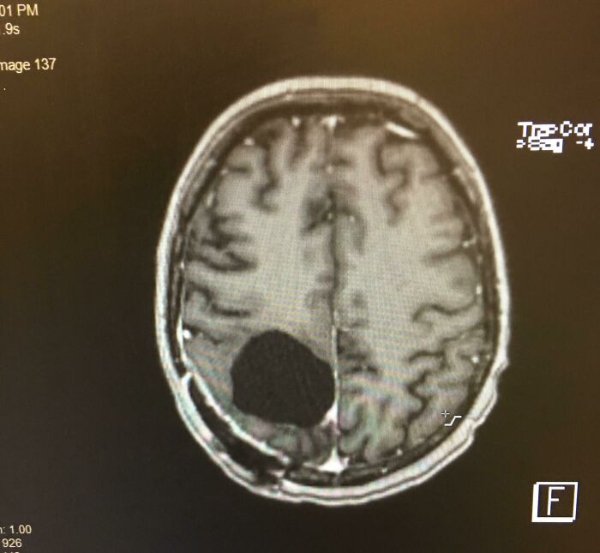

Fascinating Medical Photos